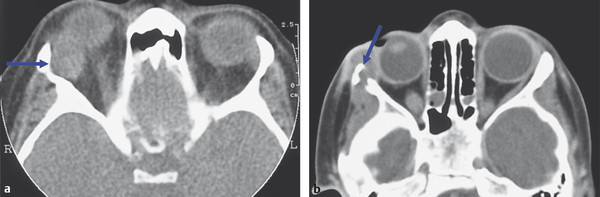

A single film does not have enough range of grayscale to display all the data from a scan. The data can be split and displayed on different films as soft tissue and bone windows. This is now done by computer manipulation of images stored on discs and viewed on computer screens. Bone windows should be reviewed any time a bone lesion is suspected (Fig. 18‑9a–e). Some lesions have very typical imaging characteristics seen with CT, such as the “ground glass” appearance typical of fibrous dysplasia (Fig. 18‑9f).

A number of lesions can be categorized according to their imaging characteristics, such as cystic lesions (dermoid cysts, mucoceles, lymphangiomas, parasitic cysts), isolated lesions (cavernous hemangioma, schwannoma), hyperostotic lesions (sphenoid wing meningioma, metastatic prostatic carcinoma), and lesions with calcification (varices, optic nerve sheath meningioma). This can aid in the differential diagnosis (Fig. 18‑14).